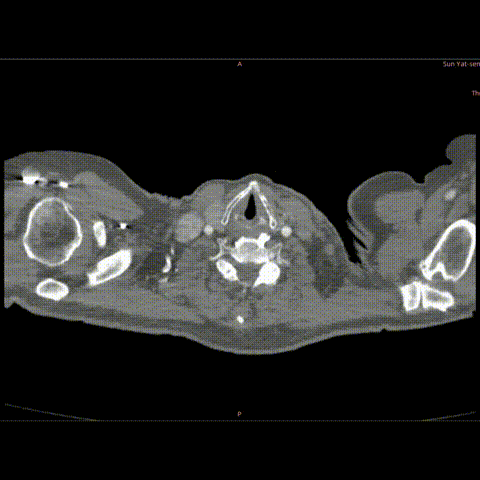

术前CTA

• 病人胸主动脉瘤破裂,病变累及LCCA;近端直径34-37mm。

• 弓上分支距离较近,INA与LCCA几乎无距离